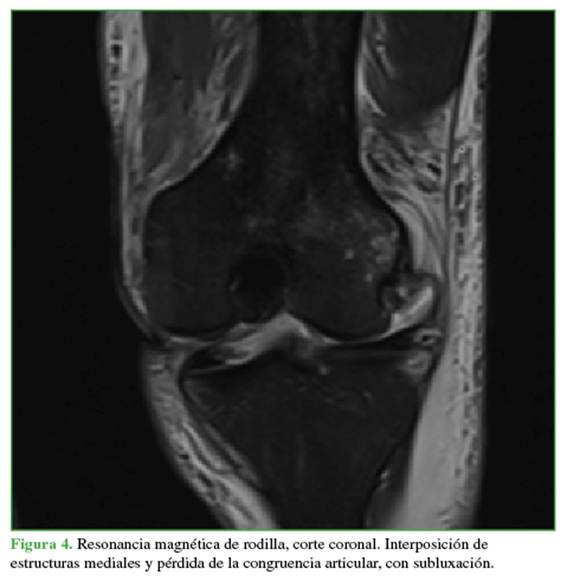

Las radiografías mostraban un aumento del espacio medial debido a la inestabilidad medial. Se ampliaron los estudios con una resonancia magnética (Figuras 4 y 5) para evaluar posibles tejidos o estructuras interpuestos y con una angiotomografía (Figura 6) para descartar una lesión vascular por el tiempo de evolución. Se observó un gran edema en los tejidos mediales, inclusive la cápsula y los tejidos mediales en la zona intercondílea, así como una persistente subluxación de la rodilla. Se descartó un compromiso vascular con integridad del paquete femoropoplíteo.